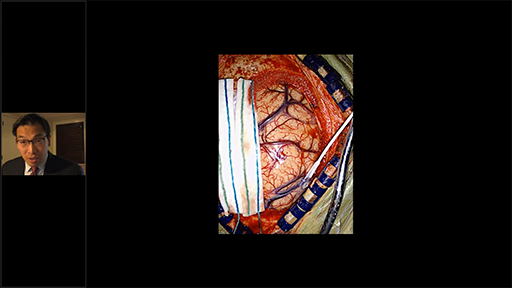

• Descripción: Nuestro invitado especial en el cuarto episodio es el Dr. Juan Alberto Paz Archila especialista en Neurocirugía. Cirugía guiada por fluorescencia en la resección de una malformación arteriovenosa del lóbulo frontal.